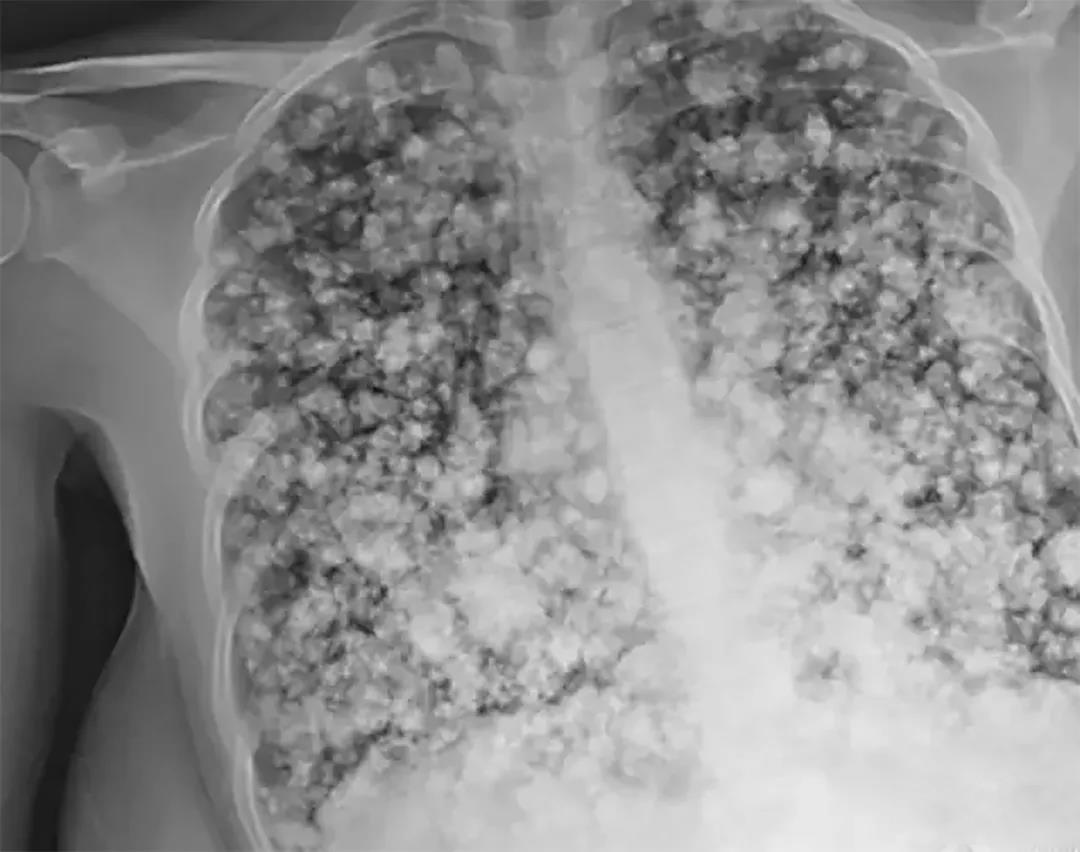

一名17岁少年因为一直咳嗽去医院看病,本以为就是风寒咳嗽,结果拍片后发现,他的肺部一片阴影,大大小小的一团一团的,像是爆米花。

医生都被眼前的片子震惊了,而少年也逐渐开始呼吸困难,医生立即采取措施,短短几小时,少年身上就插满了管子。

而医生诊断他的肺已经无法救治,虽然可以进行双肺移植,但即使找到配型,手术成功的话,也只能有5-6年的生命。

这名少年也坦言有吸食电子烟……